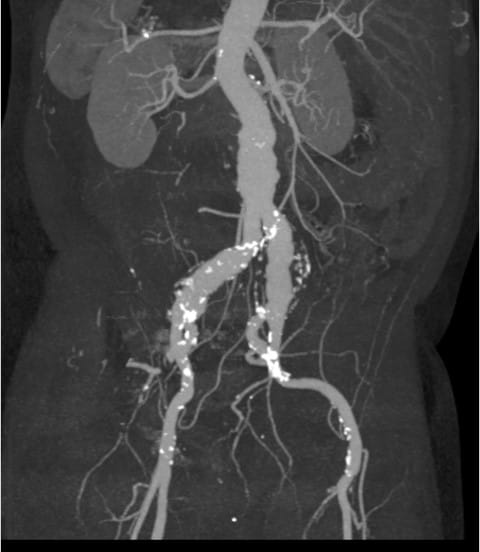

A 76-year-old male presented to UPMC for evaluation of aortoiliac aneurysm disease. His past medical history is also significant for mild emphysema, hyperlipidemia, lung and prostate cancer, and he has no family history of aneurysmal disease or connective tissue disorder. He is without symptoms of cardiac ischemia or peripheral claudication. His preoperative CT scan demonstrated the presence of a small infrarenal abdominal aortic aneurysm measuring 4.8cm, and bilateral large common iliac artery aneurysms, measuring 4cm and 3.8cm on the right and left, respectively. The internal iliac arteries were patent bilaterally (Figure 1 and 2). He underwent endovascular repair of his abdominal aortic aneurysm with placement of bilateral iliac branch endoprostheses (Gore Medical, Flagstaff AZ) for his bilateral common iliac artery aneurysms via percutaneous bilateral common femoral artery access (Figures 3-6). The patient tolerated the procedure well and was discharged on post-operative day two.

Figure 3: CTA MIP of infrarenal AAA and bilateral common iliac aneurysms